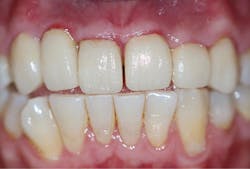

A 32-year-old male presented with having recent dental treatment abroad. Six maxillary anterior teeth had been individually crowned (figure 1).The patient’s chief complaint was severe pain in this area. He was unable to consume hot or cold food and drinks and could not use the teeth for incising. A radiographic exam revealed grossly overcontoured crowns, poorly fitting margins, and partially remaining cement (figure 2). The occlusion was evaluated and ruled out as the cause of pain. It was suspected after identifying the periapical radiolucency at the apex of the upper left lateral incisor that the pulps of some or all of the crowned teeth were affected.

Figure 1: Patient presentation with six maxillary anterior teeth individually crowned